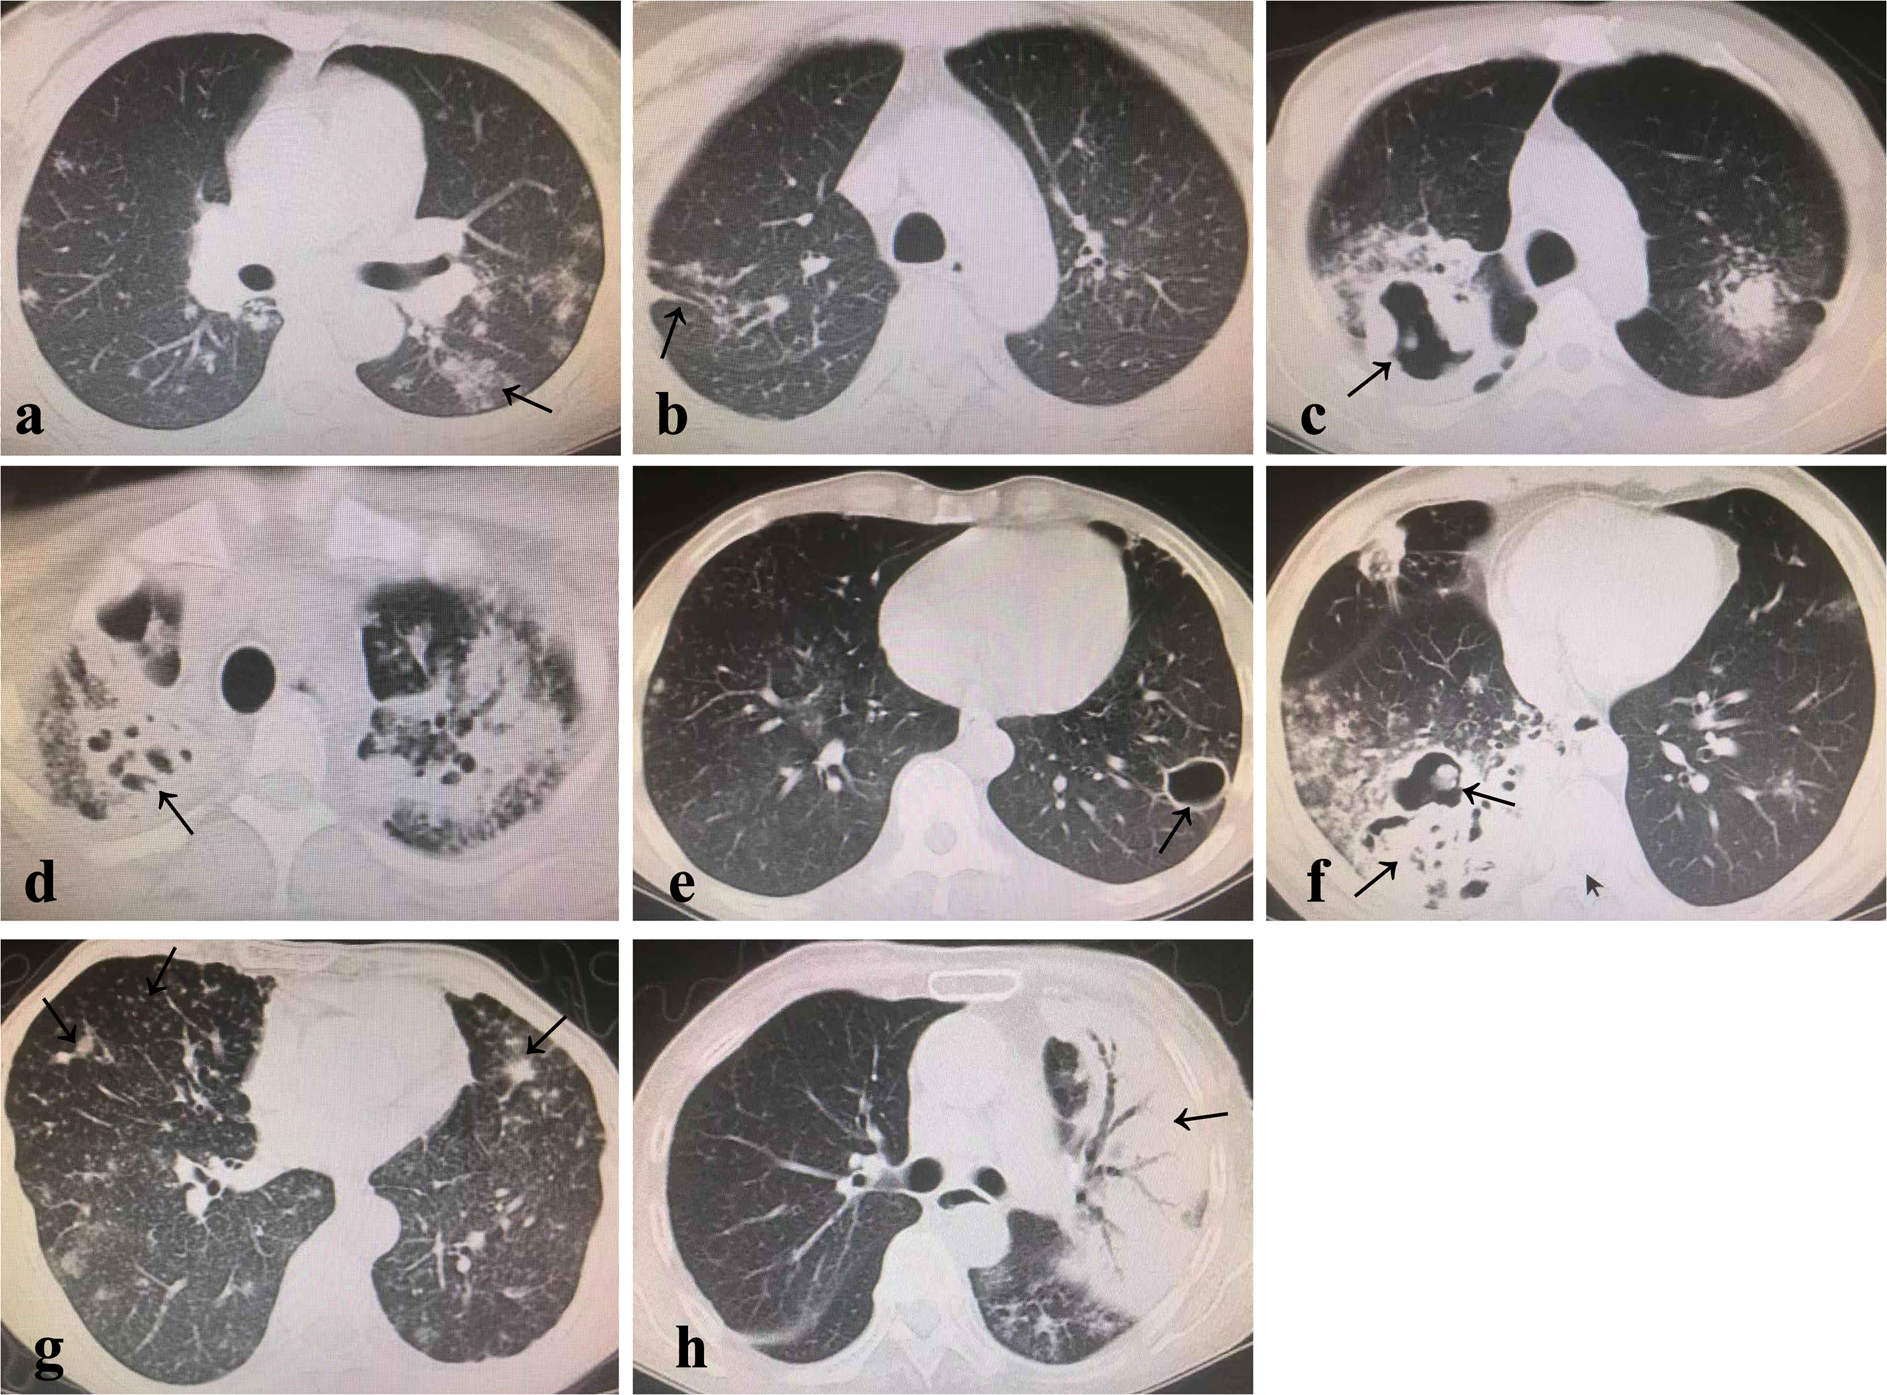

Figure 3

Patch-like shadow (a), filamentous shadow (b), thick-walled cavity (c), mouth-eaten cavity (d), thin-walled cavity (e), thick wall + mixed mouth-eaten mixed cavity (f), speckled nodular shadow (g), cheese-like lesion (h).